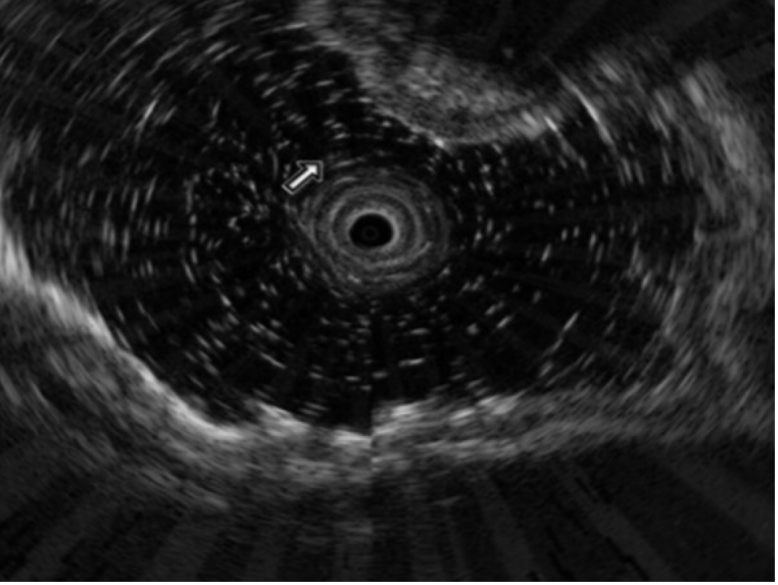

5个月后复查胃镜示:“胃底、体上部多发0.5~1.0 cm隆起性病变”,病理活检提示神经内分泌肿瘤,故建议患者到普外科行手术治疗。患者遂接受外科手术,行近侧胃大部分切除术。术中见胃底、胃体多个大小不等隆起性病变,最大者约1.0 cm×0.8 cm,表面光滑、质软。术中探查肝、胆、胰、脾未见明显异常。术后病理提示神经内分泌肿瘤,癌组织部分侵及黏膜下层,上下切缘未见癌组织,淋巴结未见癌转移(0/2)。随访至今,未见远处转移,最近一次胃镜提示:食管-胃吻合口黏膜光滑,下方小弯侧可见一大小约1.5 cm×3.0 cm黏膜隆起。超声胃镜提示:吻合口下方隆起处黏膜层、黏膜下层结构不清呈中等偏低回声,局部未见肿大淋巴结(图2)。病理结果示:慢性炎症并灶性神经内分泌肿瘤复发。

图2. 术后随访超声胃镜提示:未见淋巴结转移